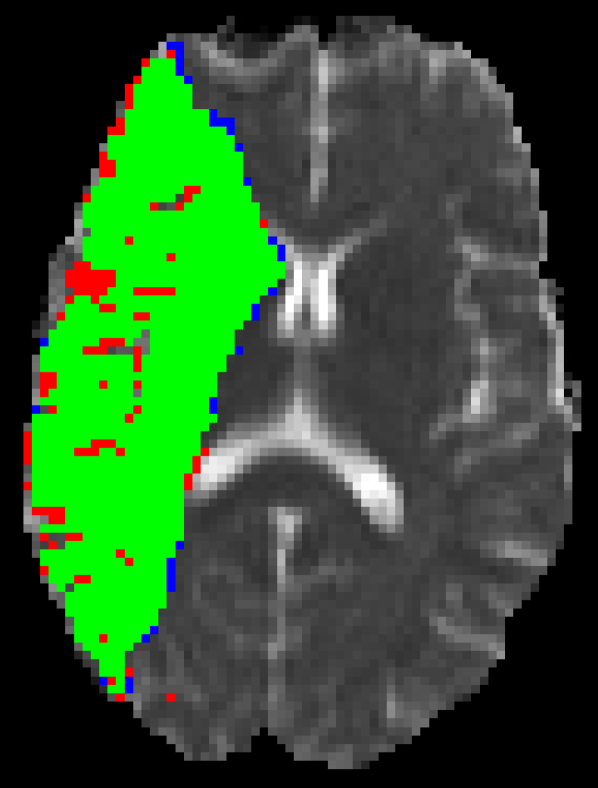

Figure 5 shows qualitative results of four representative segmentation examples from the proposed method. In general, the majority of the lesion is correctly segmented with minor border and small hole inaccuracies as seen in cases 11 and 26. Other less typical errors include under or oversegmentation of the lesion, as seen in case 2 where false positives are found on the upper part of the lesion. In the example of case 15, the lesion is undersegmented due to a confounding unusual appearance of some parts.

Refer to caption

(a) Case 2

(b) Case 11

(c) Case 15

(d) Case 26

Figure 5: Output segmentation masks of representative cases from the training images of ISLES 2015 SPES dataset. On all images, true positives are denoted in green, false positives in red and false negatives in blue.